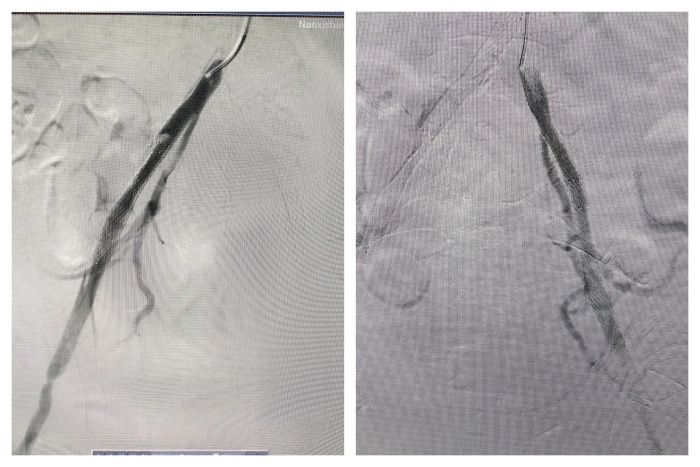

(图片3:术中左右髂动脉分别置入支架)

然而,医生们并未退缩,他们凭借着丰富的经验和精湛的技术,另辟蹊径,从上往下成功找到真腔,并顺利完成了手术。在胸主动脉近端置入覆膜支架一枚,覆盖内膜破口;开通闭塞的左髂总动脉并置入支架;右髂动脉细小真腔内也成功置入支架。手术成功封堵住主动脉内膜破口并恢复下肢供血,挽救了胡某的生命并保住了他的下肢。